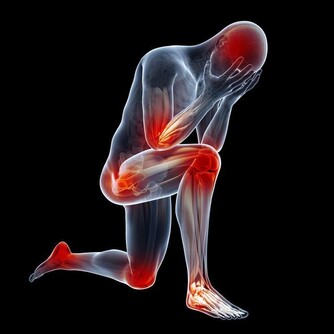

1、毒素使人患病

天長日久,臟腑被毒素侵襲後,出現失調,運作變的不順利。當毒素累積到身體無法負荷時,就會發生疾病了。